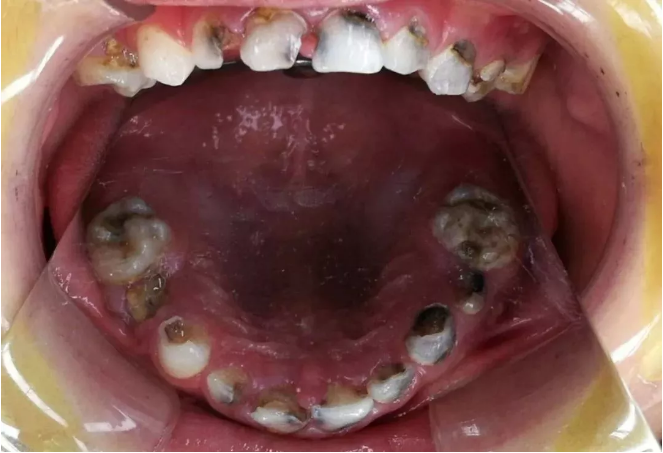

最近,一組照片讓幫幫看得觸目驚心!

小小年紀(jì),牙齒就能壞到這種程度?真是令人意想不到。據(jù)衛(wèi)計(jì)委2018年調(diào)查顯示:5歲兒童齲齒的比例竟然高達(dá)70%以上!